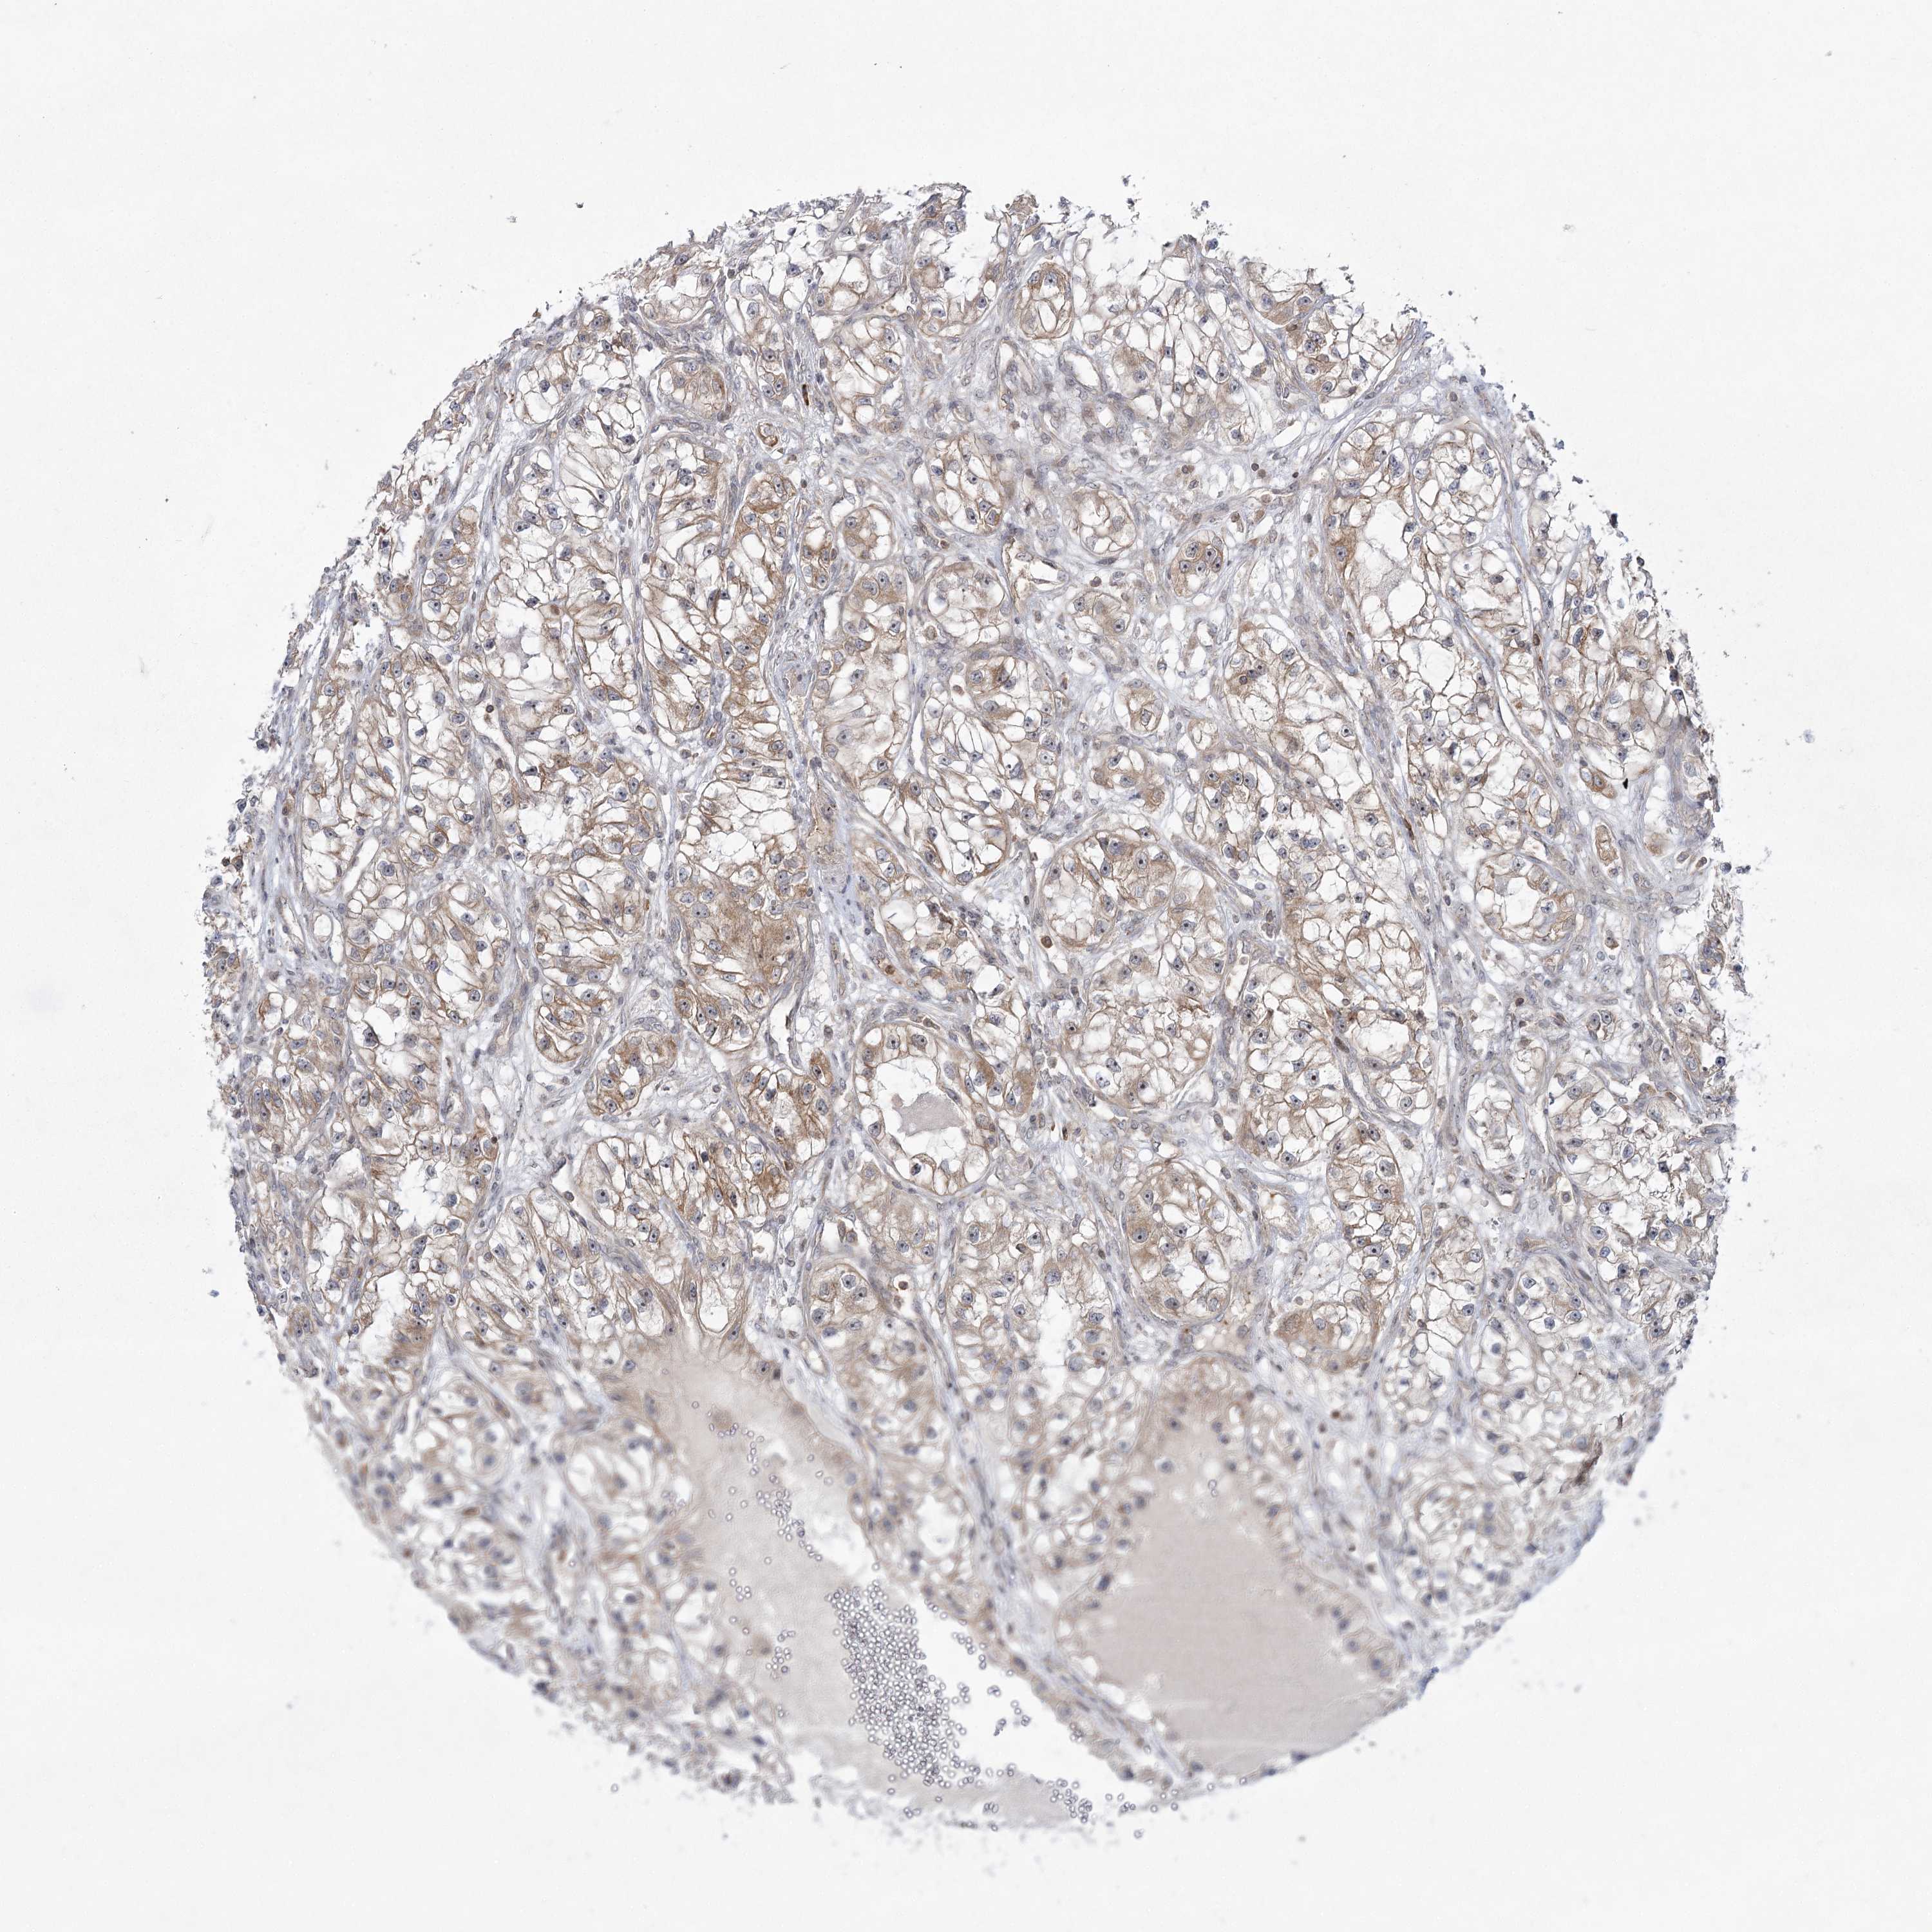

KIDNEY RENAL CLEAR CELL CARCINOMA (VALIDATION) - Interactive survival scatter ploti

The Survival Scatter plot shows the clinical status (i.e. dead or alive) for all individuals in the patient cohort, based on the same data that underlies the corresponding Kaplan-Meier plots. Patients that are alive at last time for follow-up are shown in blue and patients who have died during the study are shown in red.

The x-axis shows the expression levels (FPKM) of the investigated gene in the tumor tissue at the time of diagnosis. The y-axis shows the follow-up time after diagnosis (years). Both axes are complimented with kernel density curves demonstrating the data density over the axes. The top density plot shows the expression levels (FPKM) distribution among dead (red) and alive patients (blue). The right density plot shows the data density of the survived years of dead patients with high and low expression levels respectively, stratified using the cutoff indicated by the vertical dashed line through the Survival Scatter plot. This cutoff is automatically defined based on the FPKM cutoff that minimizes the p-score. The cutoff can be changed by dragging the vertical line or by entering a cutoff value in the square labeled "Current cut-off".

Under the Survival Scatter plot the p-score landscape (black curve; left axis) is shown together with dead median separation (red curve; right axis). Dead median separation is the difference in median mRNA expression between patients who have died with high and low expression, respectively. It is calculated as follows: median FPKM expression of dead patients with high expression - median FPKM expression of dead patients with low expression. This is intended to aid the user in visually exploring custom cutoffs and the associated p-scores and dead median separation.

Individual patient data is displayed and can be filtered by clicking on one or more of the category buttons on the top of the page. Categories describing expression level and patient information include: high, low, alive, dead, female, male and tumor stages. The scale of the x-axis can be toggled between linear and log-scale by clicking on the "x log" button. Mouse-over function shows TCGA ID, patient information and mRNA expression (FPKM) for each patient.

& Survival analysisi

Kaplan-Meier plots summarize results from analysis of correlation between mRNA expression level and patient survival. Patients were divided based on level of expression into one of the two groups "low" (under cut off) or "high" (over cut off). X-axis shows time for survival (years) and y-axis shows the probability of survival, where 1.0 corresponds to 100 percent.

SYTL1 is not prognostic in Kidney Renal Clear Cell Carcinoma (validation)

: 5.47

Average pTPM 5.6

Number of samples 100